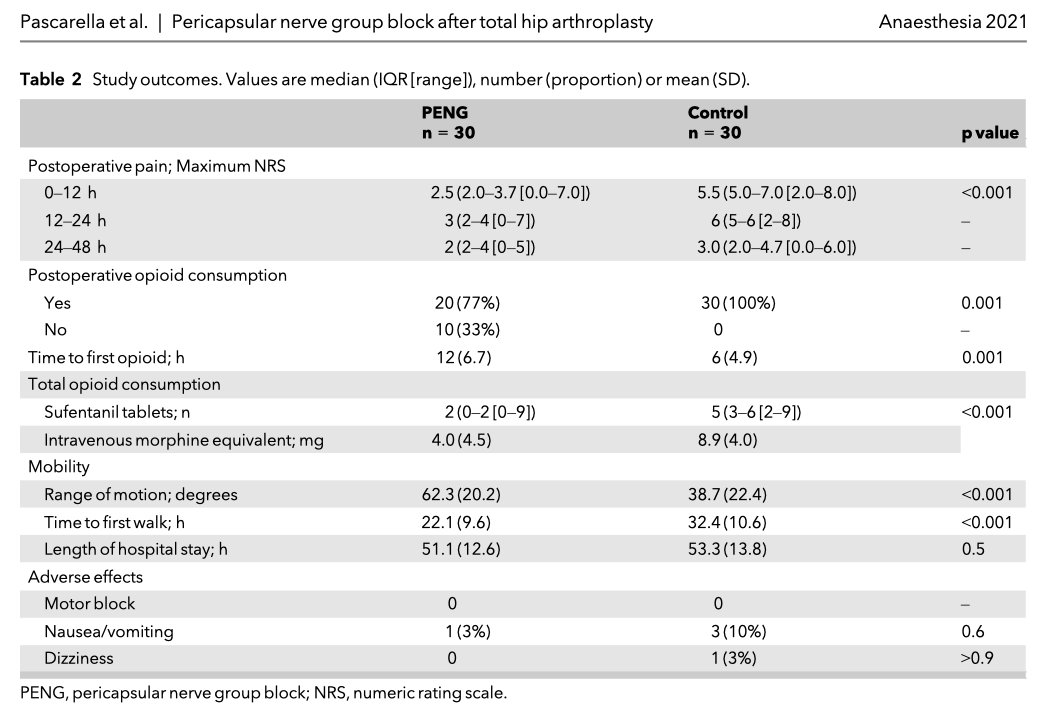

🔐This new randomised trial from Dr Giuseppe Pascarella suggests the PENG block is an effective opioid sparing analgesic technique that allows early postoperative mobilisation. Worth considering as a valid analgesia option for fast-track hip surgery protocols? 🔗…-publications.onlinelibrary.wiley.com/doi/10.1111/an…

Two recent comparative trial supporting PENG block for hip arthroplasty Randomized comparison between pericapsular nerve group (PENG) block and suprainguinal fascia iliaca block for total hip arthroplasty rapm.bmj.com/content/early/… …-publications.onlinelibrary.wiley.com/doi/epdf/10.11…

Letter: Defining the optimal spread of local anesthetic during pericapsular nerve group (PENG) block may help to avoid short-term motor block Letter: ow.ly/hFRD50GecGP In reply to: ow.ly/E7Bo50GecZE #regionalanesthesia Dr Giuseppe Pascarella Raj Gupta, MD, FASRA Eric Schwenk, M.D., FASA

An interesting discussion about the motor sparing effects of PENG block 🔗 …-publications.onlinelibrary.wiley.com/doi/epdf/10.11… ESRA | European Society of Regional Anaesthesia Dr Amit Pawa💉🎙️ 𝘈𝘯𝘢𝘦𝘴𝘵𝘩𝘦𝘴𝘪𝘢 ASRA Pain Medicine